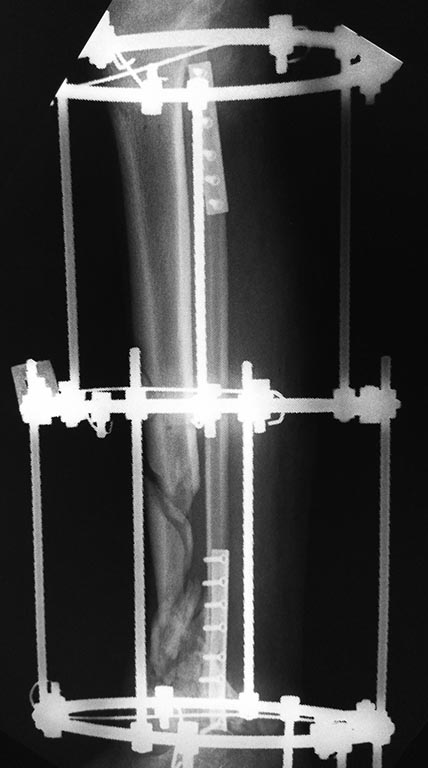

Добрый вечер уважаемые коллеги. Представляю Вам пациента 35 лет после кататравмы , которая случилась в декабре 2016 г.

Длительное время лечился в стационаре, множество повреждений поэтапно было оперировано.

Что касаемо голени, перелом был закрытый. Выполнена открытая адаптация отломков б/берцовой кости, комбинированный остеосинтез костей голени. Рана зажила первично.

Представляю вам снимки первичные при поступлении и голень в аппарате на сегодняшний день. Тактическое предложение следующее: